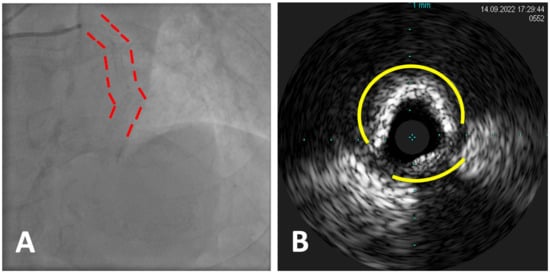

5.2. Case 1

- Multiple subocclusive calcified stenoses of proximal and mid LAD and a CTO of the first diagonal (Figure 3A).

- Multiple subocclusive calcified stenoses of all the Cx with an 80% ostial stenosis of a big OM.

- Subocclusive calcified stenosis of the distal RCA and proximal PDA.